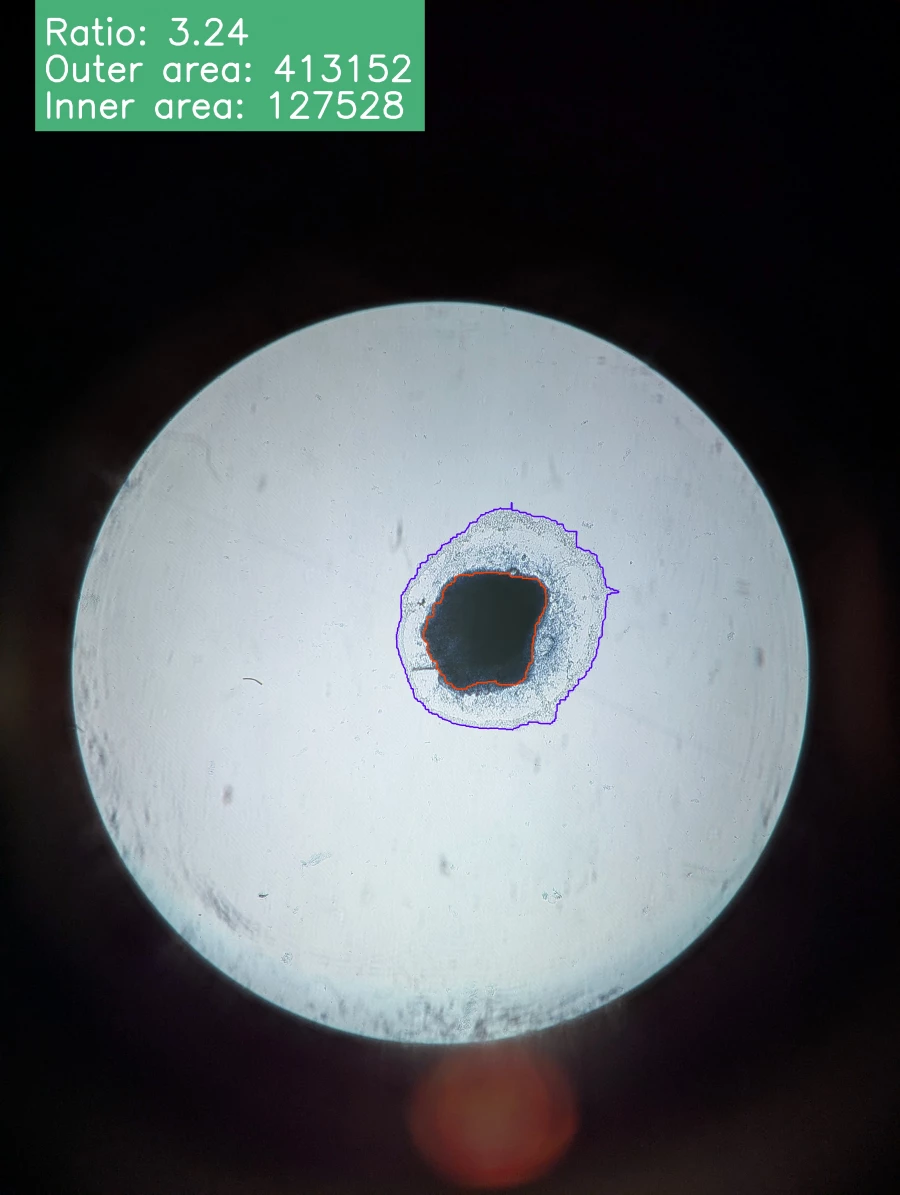

Наука. Снимки эксплантов

Когда эксплант растет в питательной среде, вокруг него формируется так называемая «зона роста» – тонкий, почти прозрачный слой делящихся клеток. Размер зоны – это ключевой показатель жизнеспособности клеток и показывает их реакцию на внешние воздействия, например, на новое лекарство.

Приложение для ученых

Сейчас ученые вынуждены вручную анализировать несколько планшетов с образцами под микроскопом: обводить зоны роста, подсчитывать их площадь. На одном планшете может находиться не менее 24 эксплантов. Это монотонная и трудоемкая работа, напоминает бумажную волокиту и отнимает у лаборантов несколько дней, которые они могли бы посвятить исследованиям.

«Мы создаем автоматизированную систему для анализа изображений эксплантов, – рассказывает Михаил Макеев. – Пользователь сможет загружать снимки на наш онлайн-сервис. Затем алгоритм на основе машинного обучения автоматически распознает и обводит эксплант и зону роста. После этого он проводит все необходимые расчеты и выдает готовый отчет. Это освободит время для более сложных научных задач».